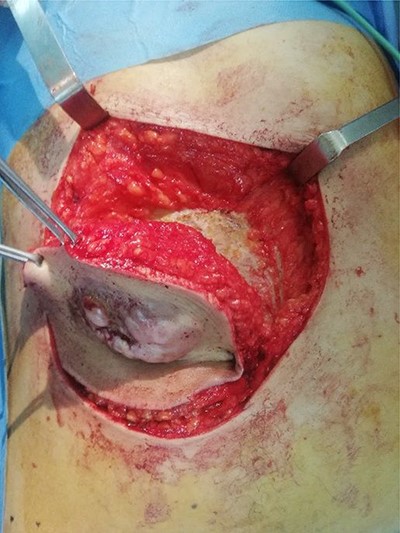

Per-operative view showing the resulting wound defect (a) repaired by primary closure (b)

A 45-year-old woman complained of the occurrence of a small cutaneous lesion on the AAW evolving over the past precedent 3 years. The swelling volume had progressively increased. The physical examination revealed an oval mass with regular borders and a polylobed surface; the lesion was localized at the supra-umbilical level of AAW, and slightly lateralized on the right with dimensions of 5 cm by 3 cm (Fig. 1). The palpation revealed a hard and fixed swelling on the skin. However, it remains freely mobile regarding the deeply musculoaponeurotic plane. The histopathological findings on the skin biopsy were consistent with DFSP. The thoracic–abdominopelvic computed tomography (CT) scan did not show any metastatic lesions. The abdominal CT sections showed a well-defined enhancing soft tissue density lobulated lesion measuring 5.8 × 1.5 cm and arising from the AAW. The lesion presented a discreetly heterogeneous enhancement. It infiltrated subcutaneous tissue without any involvement of the musculoaponeurotic plane which remained distant from the lesion (Fig. 2). The patient underwent WLE with minimal macroscopic safety margins of 3 cm from the visible and palpable limits of the tumor (Fig. 3). The resulting defect was repaired with primary closure by advancing the adjacent tissue. Indeed, the cutaneous and subcutaneous tissue under the wound caudal edge was raised off anterior abdominal aponeurosis which facilitated flapping advancement and wound-free-tension coverage (Fig. 4a). We obtained an acceptable esthetic result in the form of a transverse mid-abdominal scar (Fig. 4b). The recovery was simple. The specimen histopathology revealed a characteristic of DFSP appearance with spindle cells in a storiform arrangement (Figs 5 and 6). The immunohistochemistry confirmed the diagnosis by revealing cluster differentiation 34 (CD 34) expression (Fig. 7). The margins are microscopically safe. The final decision of the multidisciplinary meeting consisted of surveillance. After 4 years of follow-up, no locoregional or distant recurrence was observed.

Surgical resection is the main treatment for DFSP. It should take into account the potential infra-clinical extensions of the tumor, which might originate the local recurrence. The standard treatment consists of a WLE. The optimal width of the resection margin is controversial. However, the majority of authorities recommend margins of 2–4 cm [8, 9]. The management of defects resulting from tumor excision is a major concern, its’ reparation depends on the size and thickness of the resulting wound. Indeed, in the case of a small and superficial lesion accounting for the majority of DFSP in abdominal location [4], the lesions are often treated by WLE and primary closure without the required resect of the full abdominal wall thickness. In our patient, the primary closure was feasible for two main factors. First, the defect was partial thickness and spreading aponeurosis. Second, the laxity of the abdominal wall allows free-tension closure. However, in the case of a large tumor with deep invasion or recurrent tumor, a large full-thickness excision is recommended and reconstruction is required [4].